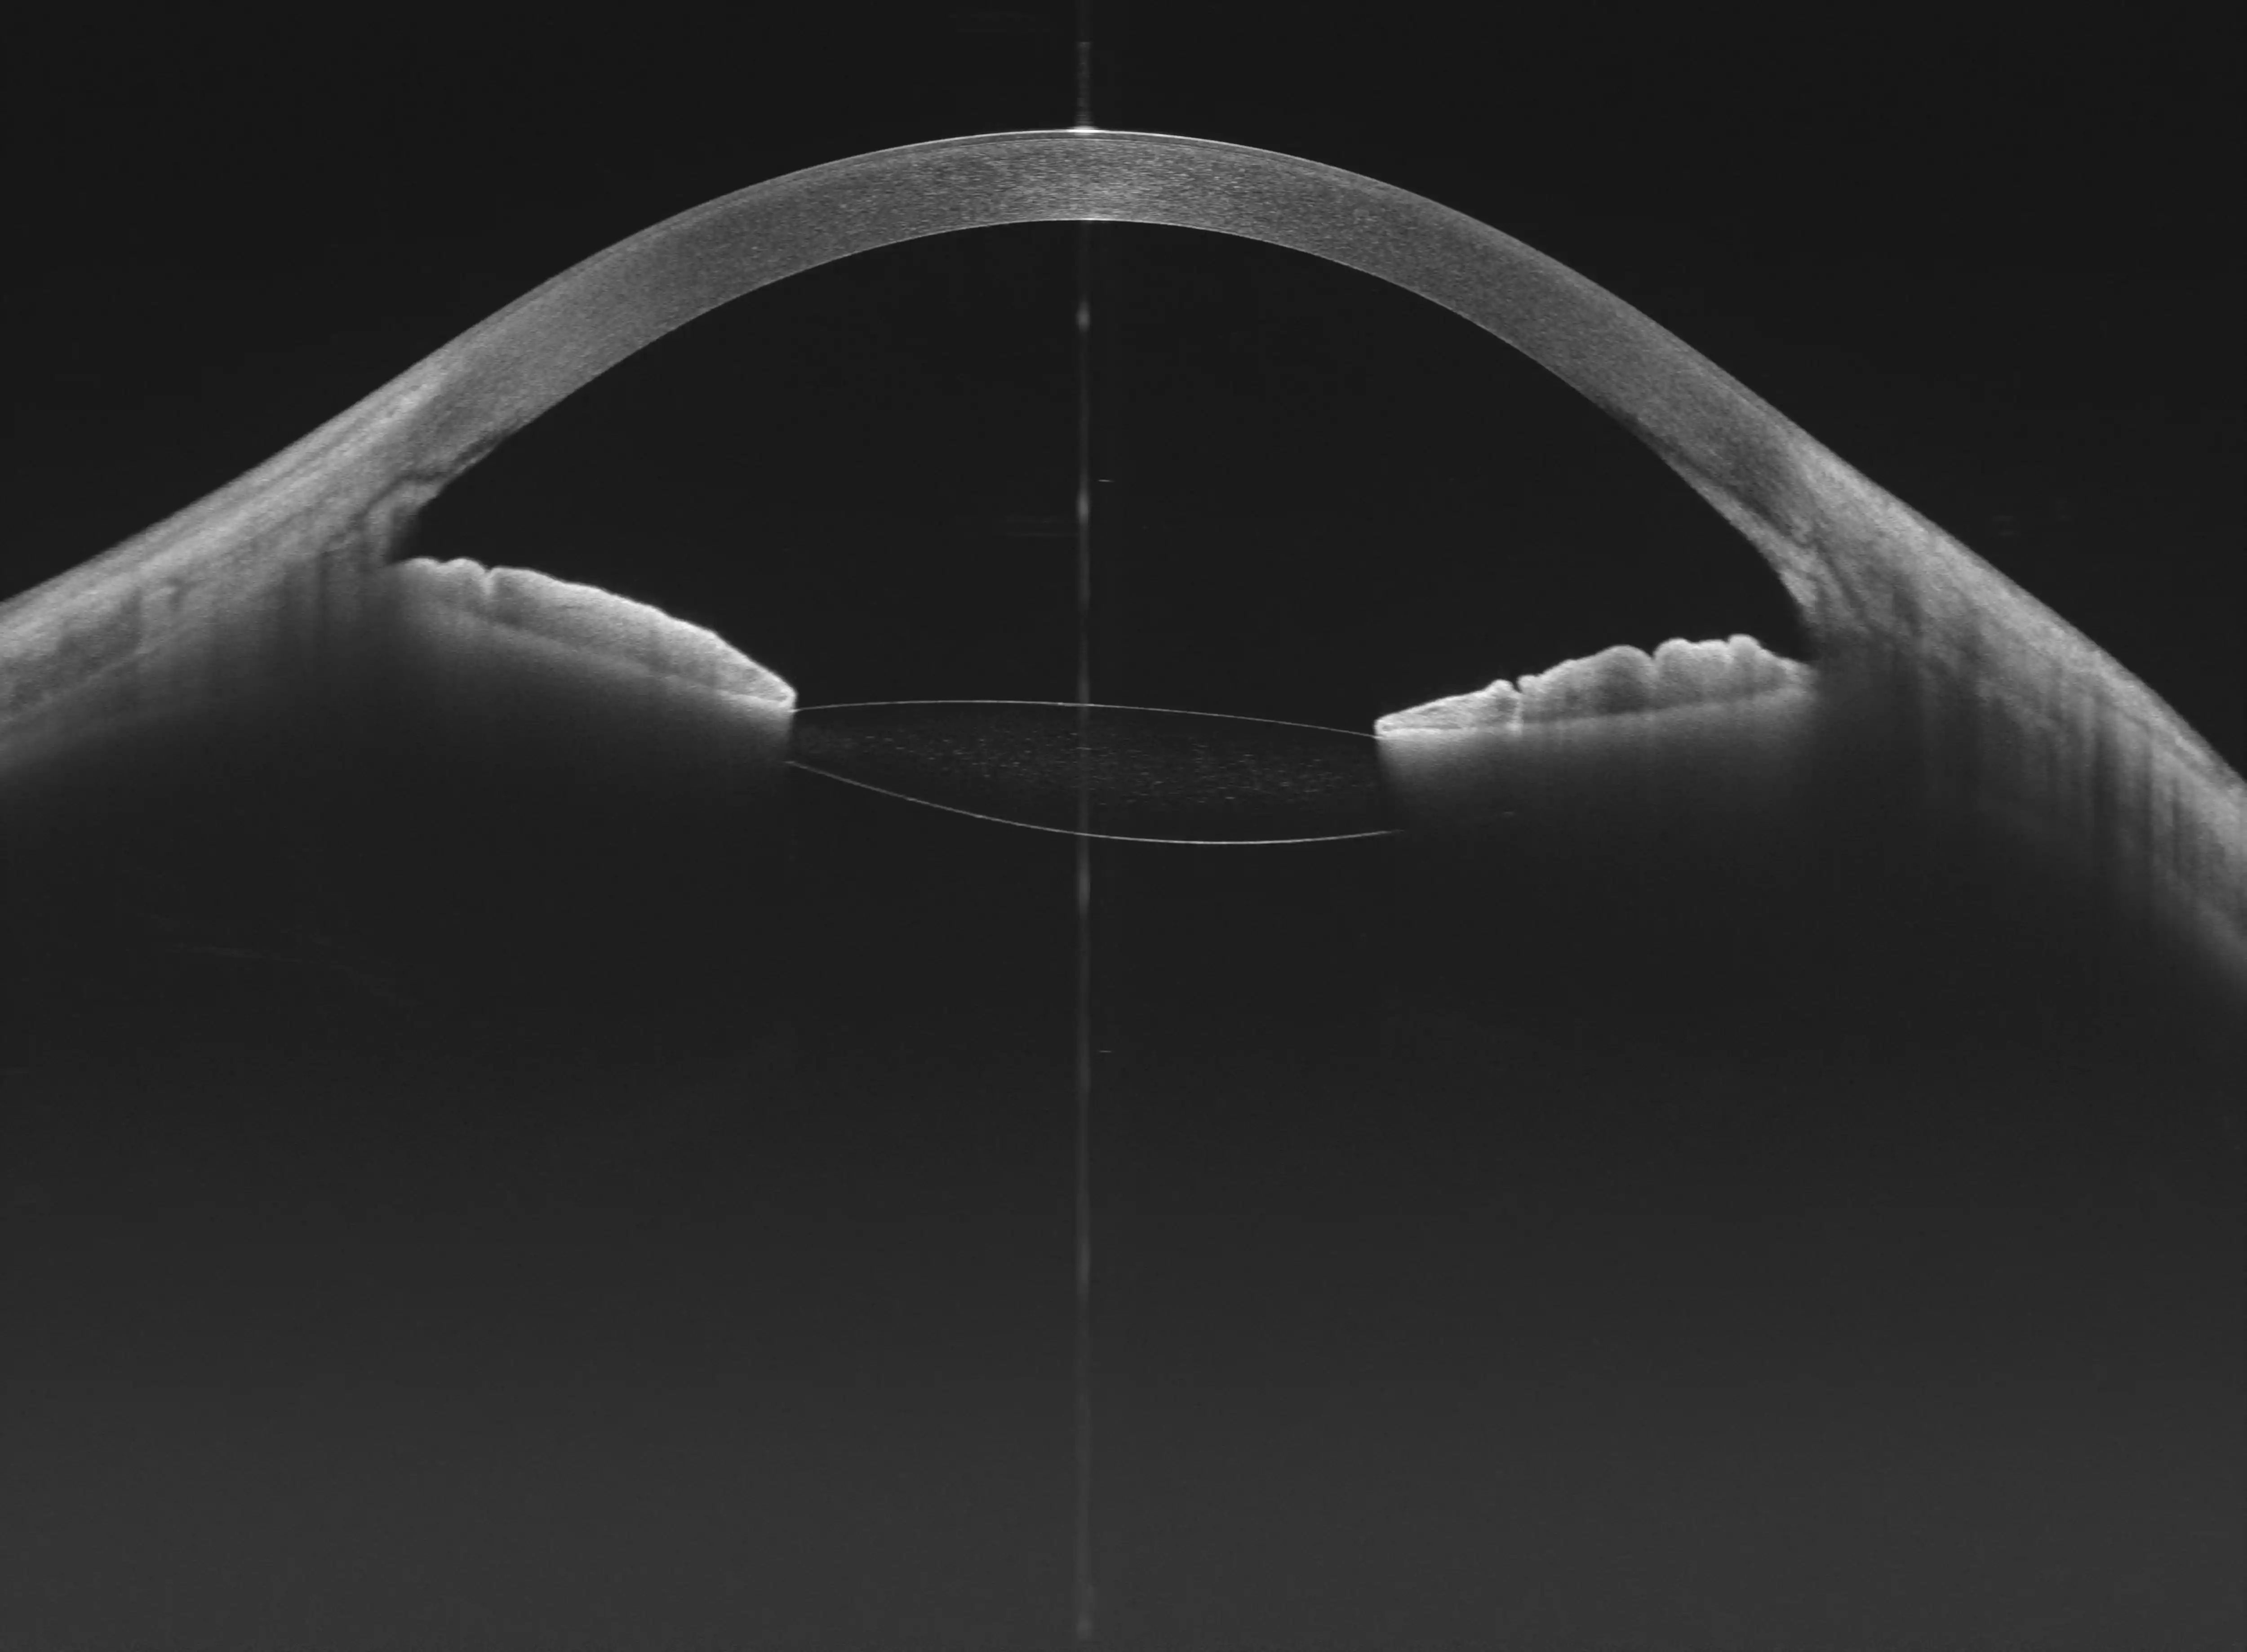

Głęboka penetracja

Urządzenie zapewnia większą głębokość skanu w tylnym odcinku (12 mm) i przednim odcinku (15 mm), co jest szczególnie korzystne w obrazowaniu ciała szklistego, naczyniówki oraz struktur przedniego odcinka

Optymalny balans

Stanowi idealny wybór do kompleksowego zastosowania OCT w jednym urządzeniu, oferując pełnozakresowe obrazowanie przedniego i tylnego segmentu oka

Analiza Segmentu Przedniego (AS)

Pomiary ilościowe, parametry panoramiczne, mapa grubości rogówki, głębokość komory przedniej i kąt przesączania